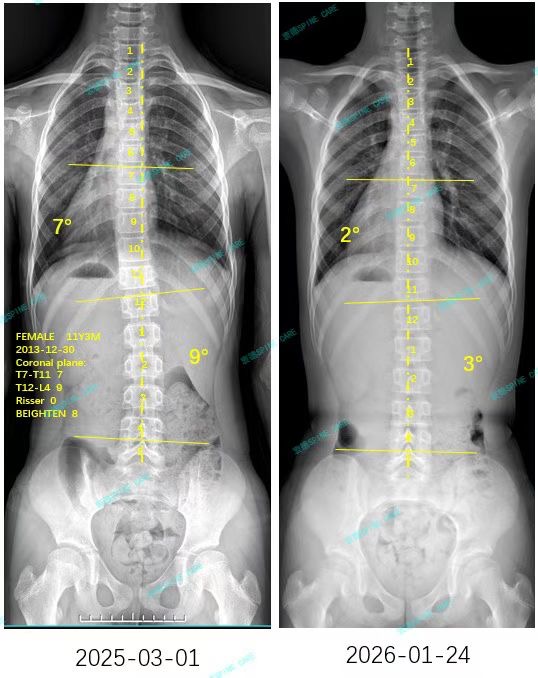

衷德脊柱,我们只关注侧弯保守治疗~

Zhongde Spine, bending no breaking ~